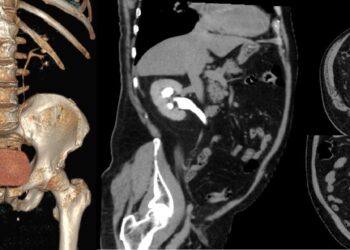

URO-CT sau urografia prin tomografie computerizată este o investigație medicală imagistică folosită pentru a evalua tractul urinar al unei persoane. ...